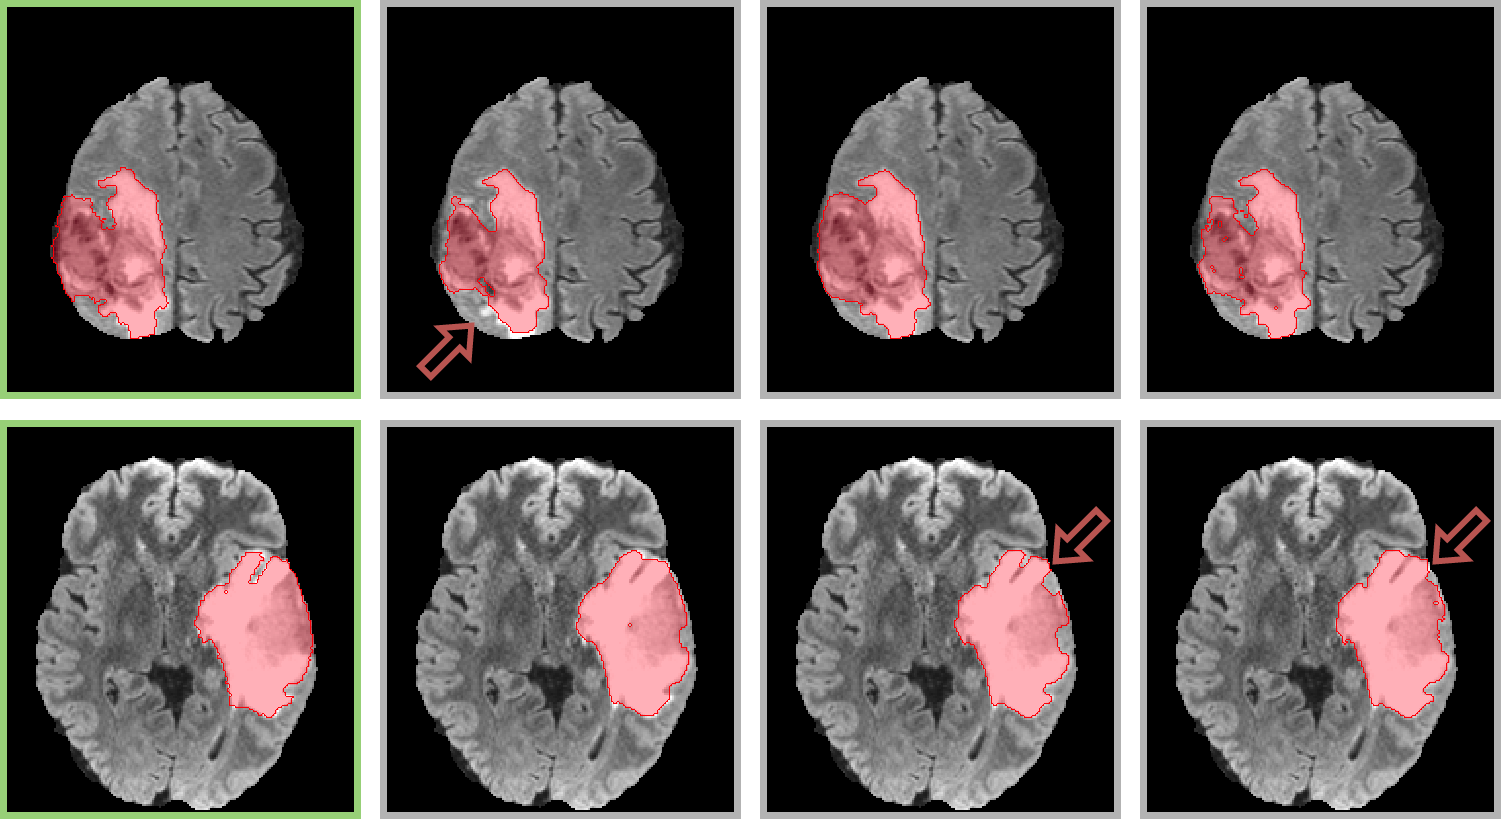

Figure 5 shows qualitative results for two samples of the test set of our private dataset. The top row contains an example where the MS-FLIM segmentation performs poorly compared to nnU-Net and DeepMedic, missing a region (arrow). Alternatively, the bottom row shows a case that MS-FLIM achieved better results than nnU-net and DeepMedic. Finally, the figure illustrates that our model can achieve better results in several situations and that the main distinctions between our results and the upper-bound (SOTA deep learning models) are in the fine-grained segmentation.

|